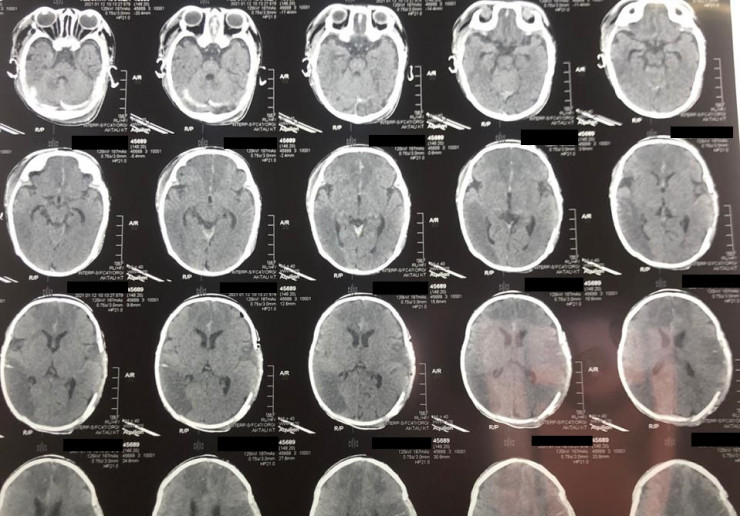

Как сообщили в больнице, у двухмесячного младенца из-за инсульта зафиксировали отек головного мозга, дислокационный синдром и кому I-II степени. Благодаря усилиям врачей 10 января состояние ребенка удалось стабилизировать. В экстренном порядке ему провели операцию по трепанации черепа, которая продлилась два часа.

Фото: lada.kz/Ербол Кенжевалов

"Такие случаи редко заканчиваются положительным результатом, но нам удалось спасти ребенка. В настоящий момент пациента перевели в отделение травматологии, он находится в среднетяжелом состоянии", - сообщил детский нейрохирург Ербол Кенжевалов.